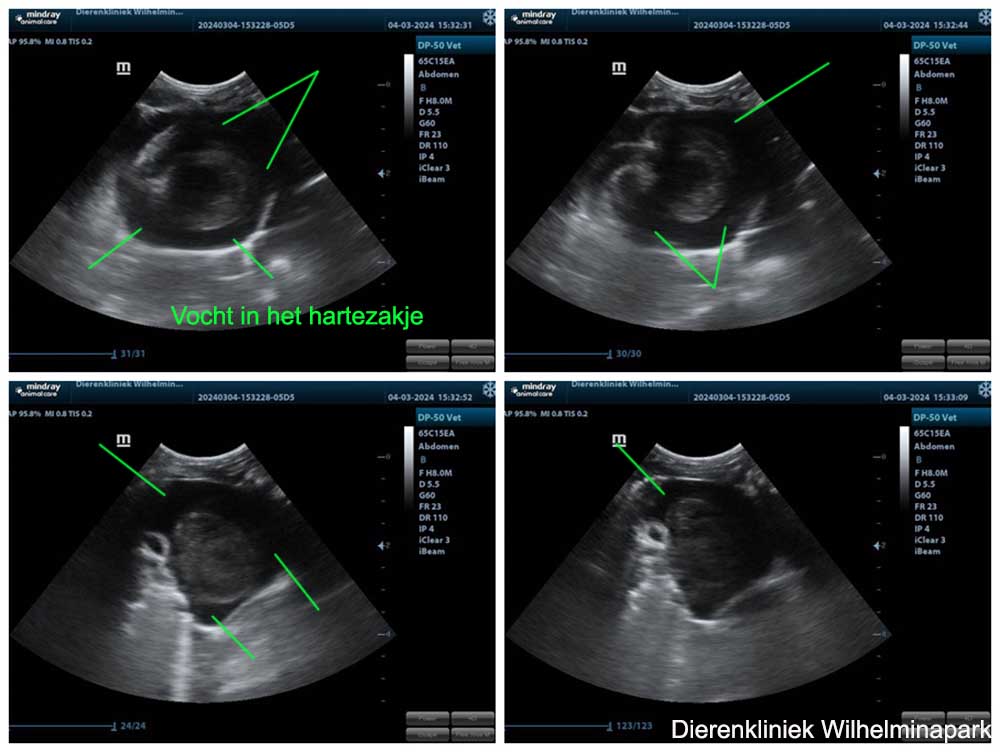

We hebben de röntgenfoto's laten beoordelen: er is een verdenking van een pericard overvuulling. Het hart is vergroot op de röntgenfoto, het advies is om een echo te maken. Met een echografisch onderzoek is een pericardovervulling goed te zien. Er zit dan vocht tussen het hart en het hartzakje.

Op de echo van het hart van Tweetie is vocht naast het hart in het hartzakje te zien - er is een pericard overvulling, zie de foto's hieronder.

We kunnen vochtafdrijvers geven bij een pericardovervulling, maar helaas verder geen andere medicijnen of behandeling aanbieden.

Bij een hart probleem zien we vaak een tik in de ademhaling.

Wat opviel bij Tweetie was een tik in de ademhaling. We zien een dergelijke tik vaak bij een cavia met vocht in de longen ten gevolge van een hartprobleem.